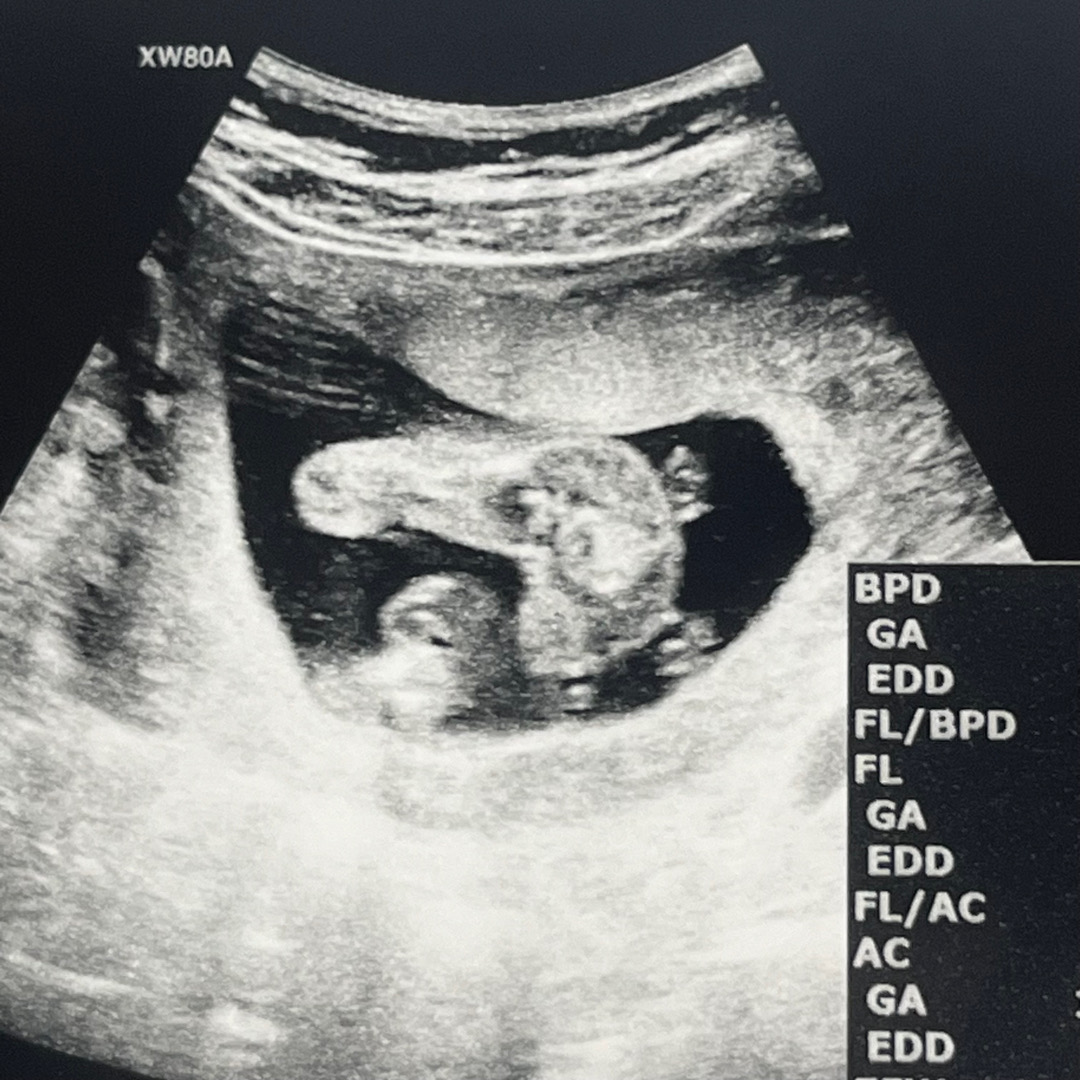

16주 진입 딸 맞겠죠~?

오늘 초음파 보고 딸 맞는거같네요~ 하셨어요! 16주면 이제 확정이겠죠?!